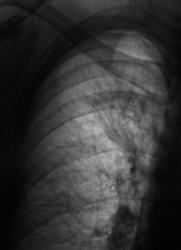

После расшифровки цифровых флюорограмм, пациент взят на контроль, дообследован. Ваше мнение уважаемые коллеги?

Можно предположить гиповентиляцию S2. Необходима КТ.

А если нет возможности сделать КТ, выполнить линейную томографию на в/долевой и сегментарные бронхи в/доли справа, бронхоскопию... В связи с этим у меня вопрос: Валентин Львович, я знаю у вас очень много случаев туберкулеза, но почему ваши лаборанты практически никогда не делают сразу срезы на бронхиальное дерево?

А где предыдущие данные, или это "с хутора"? Тогда КТ надо или бронхоскопию, если терять нечего - динамика покажет.

Вот посему, мы и предположили, наличие, как ранее называли, перибронхиального рака. Правда сейчас, он по всей видимости, отнесен к одному из видов БАР.

а по каким признакам здесь заподозрен БАР? Я почему то был уверен что это туберкулёз?

Туберкулез, в данном случае, нельзя исключить из дифряда, но он явно не первый.